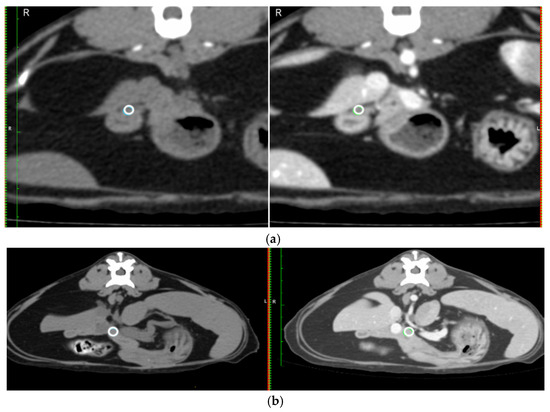

- Mean Hounsfield unit (HU) on a circular region of interest (ROI) placed over the duodenal papilla pre- and post-contrast on the transverse image (Figure 2a).

- The mean HU for the same circular ROI, pre- and post-contrast in a section of the pancreas at the level of the pancreatic body (Figure 2b).